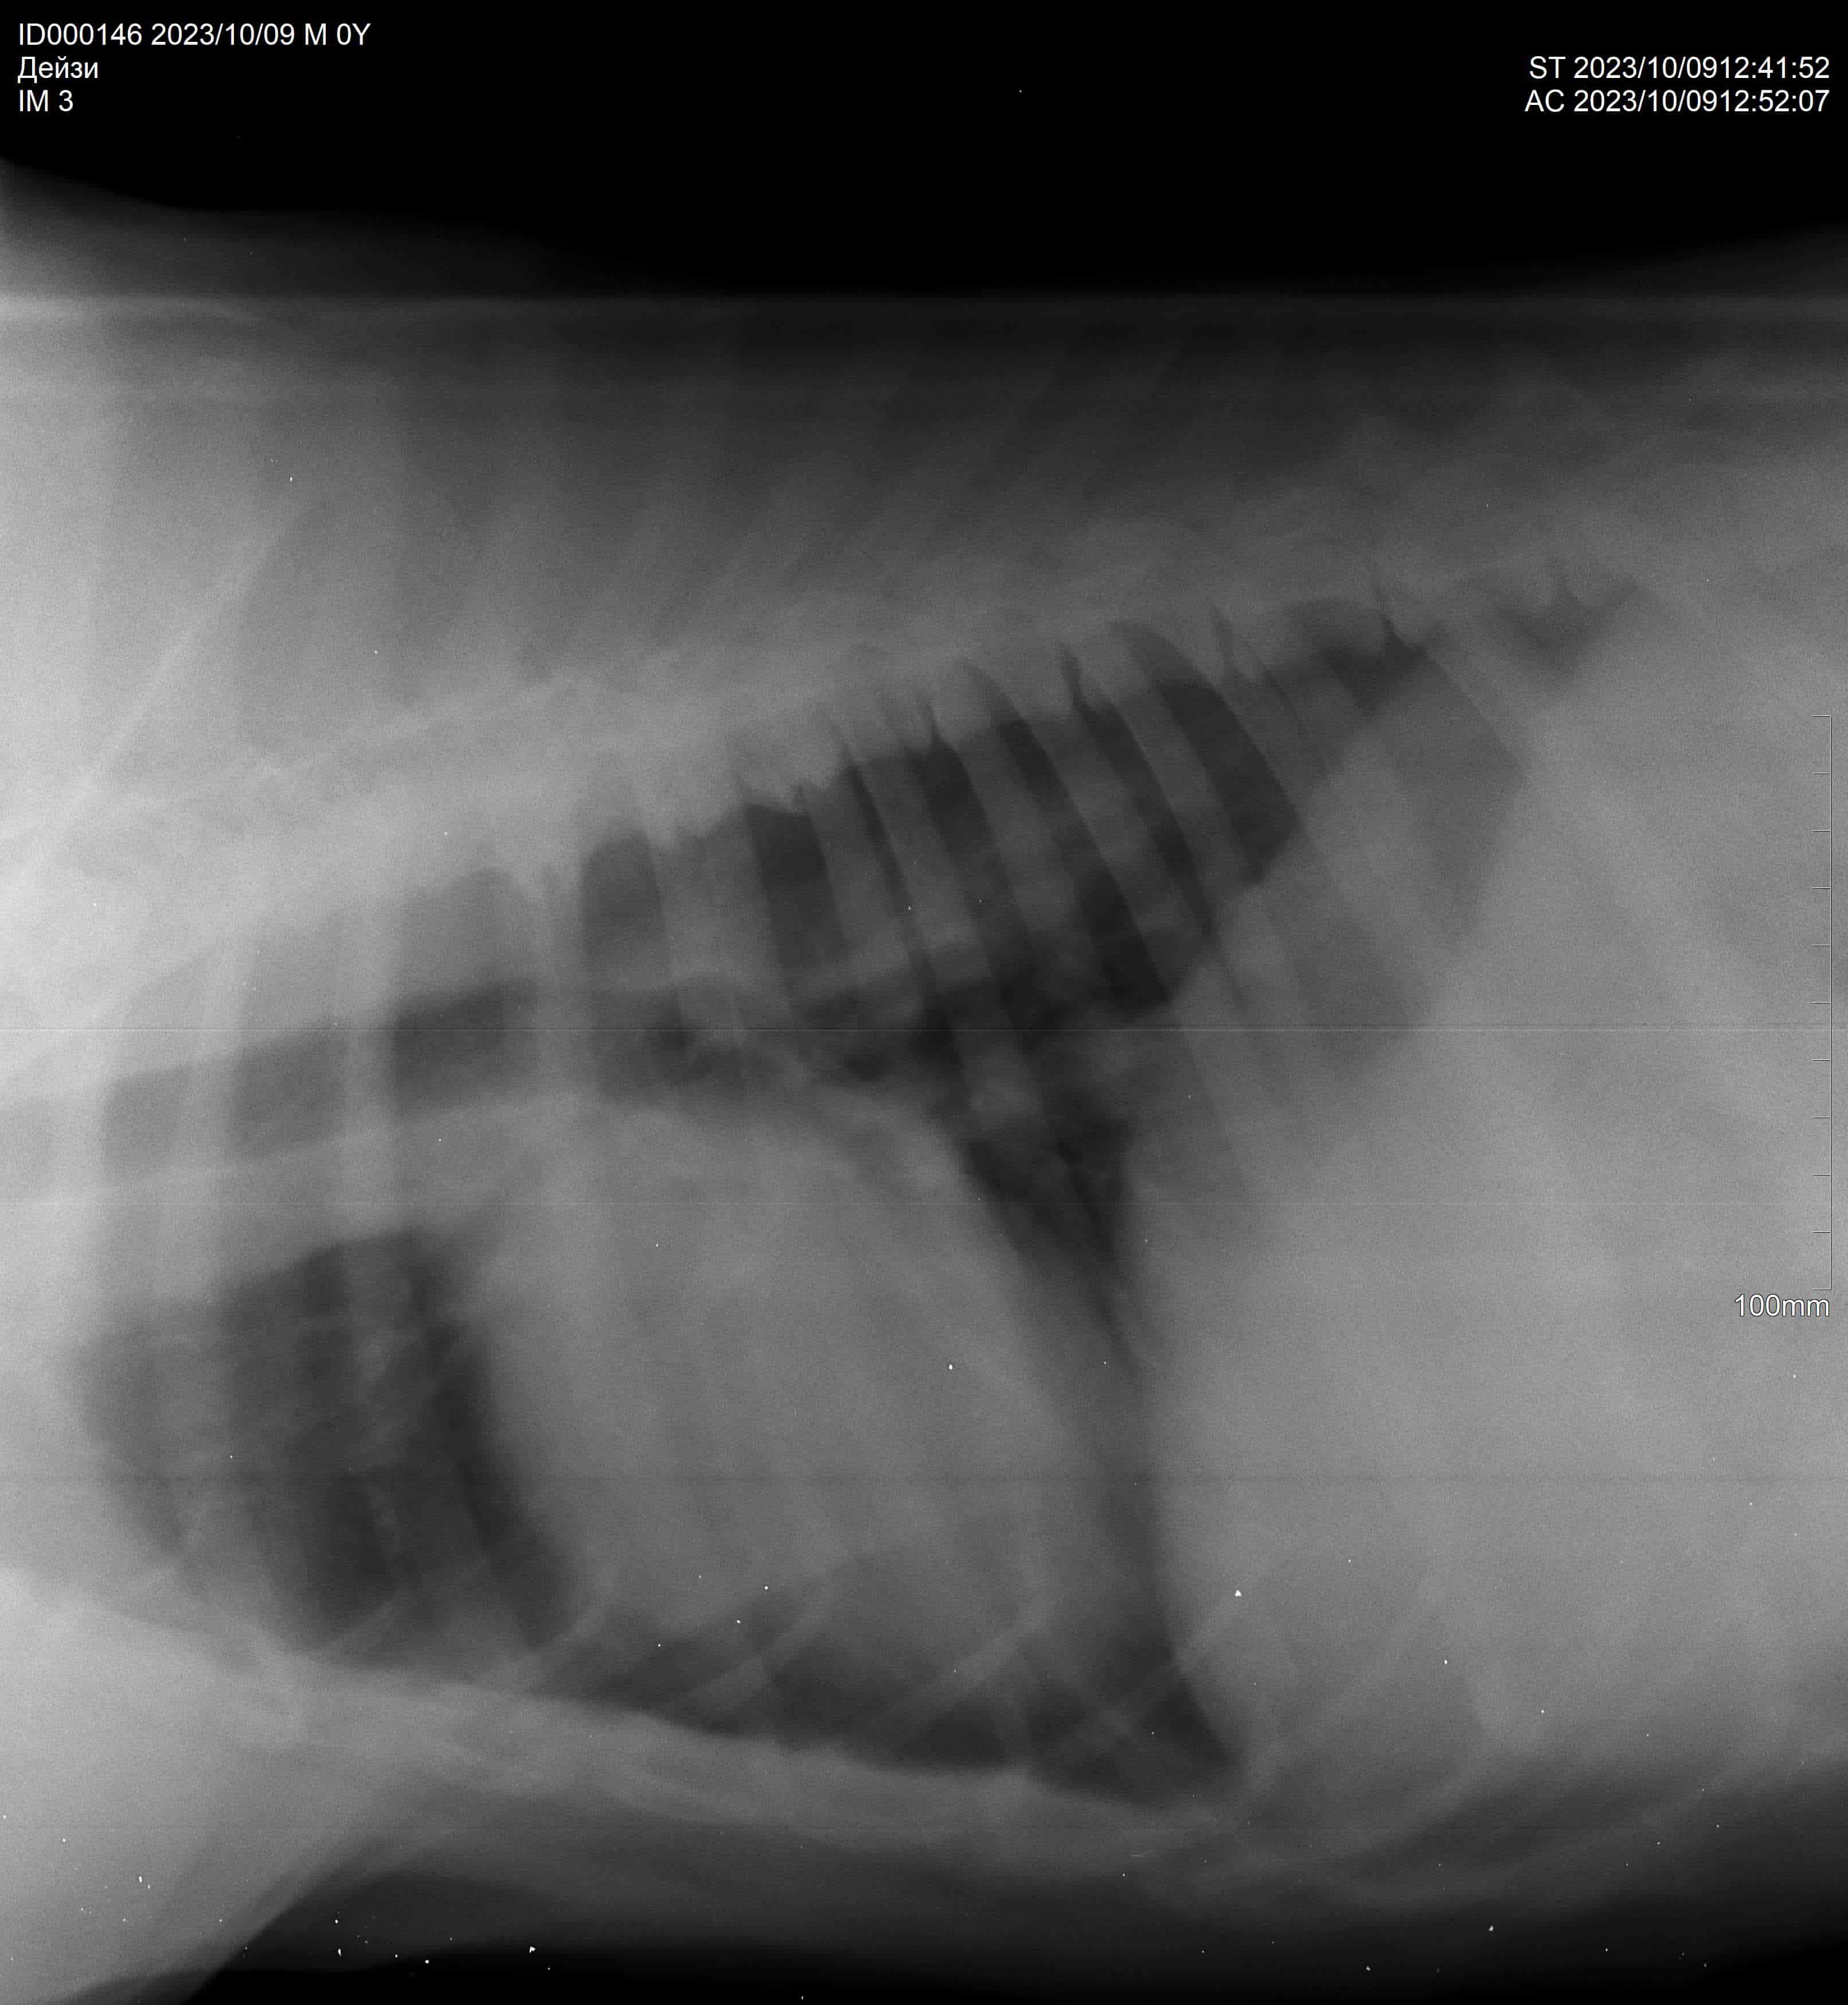

Операция и кардиография